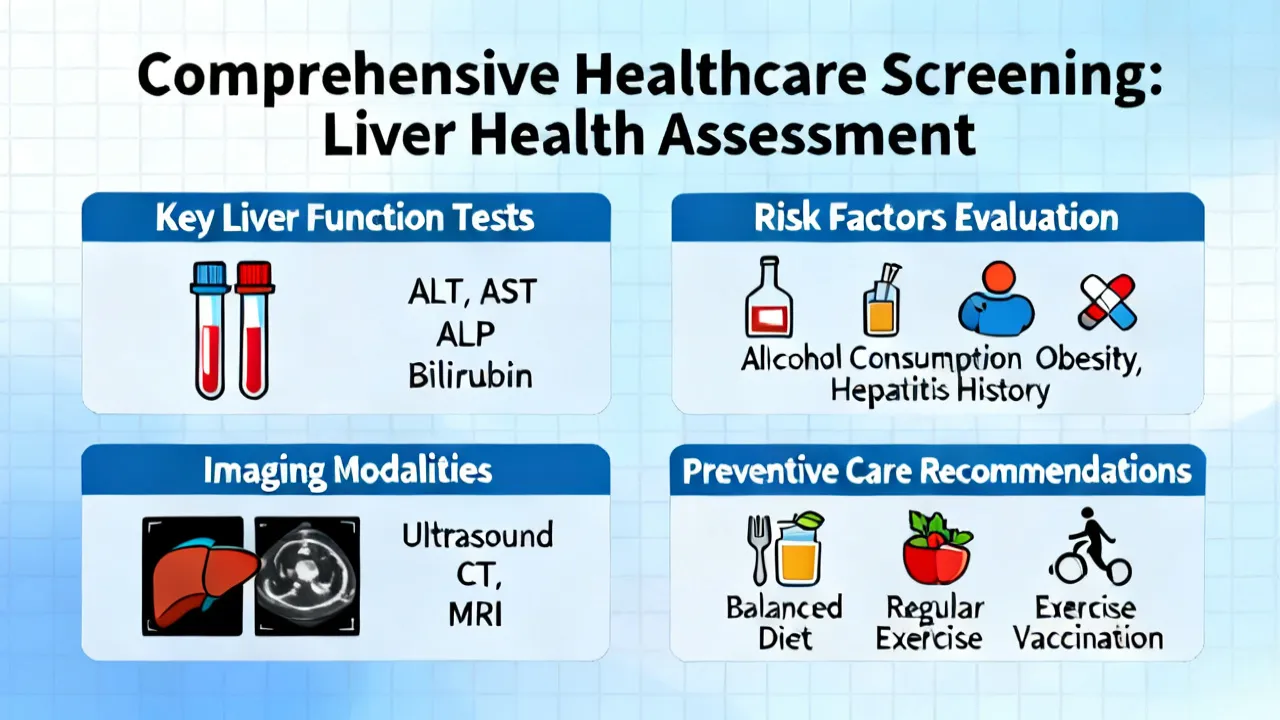

NASH HCC Screening is crucial for early detection and management of liver complications such as non-alcoholic steatohepatitis and hepatocellular carcinoma. Screening helps in identifying individuals at risk before symptoms develop. With advancements in medical technology, screening has become more precise, providing hope for better therapeutic outcomes and patient care in the ongoing battle against liver diseases.

NASH HCC screening plays a crucial role in the early detection of liver cancer associated with Non-Alcoholic Steatohepatitis (NASH). NASH is a severe form of non-alcoholic fatty liver disease that can progress to hepatocellular carcinoma (HCC), a common type of liver cancer. This article provides insights into the importance of screening, methods, and current practices in managing and identifying at-risk individuals for timely intervention.

NASH HCC Screening is a crucial process in the early detection of liver cancer associated with Nonalcoholic Steatohepatitis (NASH). As liver disease has become a growing concern, screening provides valuable insights into patient liver health, aiding in timely treatment strategies. This article delves into the significance, procedures, and advancements in NASH HCC Screening, providing a comprehensive guide from an expert's perspective.

Understanding the implications of Nash Hcc Screening is crucial in medical diagnostics, particularly for liver-related health issues. With advancements in medical technology, Nash Hcc Screening has emerged as a pivotal procedure in identifying and managing conditions affecting liver health, notably Nonalcoholic Steatohepatitis (NASH) and Hepatocellular Carcinoma (HCC). This comprehensive article delves into the significance, process, and advancements in Nash Hcc Screening, offering insights from medical experts on its role in predictive diagnostics and patient management.

Analyzing the significance of Nash Hcc Screening, this article explores its role in early detection of liver complications. "Nash", or Nonalcoholic Steatohepatitis, leads to cancer if unchecked. Early screening is key for prevention. The article offers expert insights on screening processes, benefits, challenges, and potential technological advancements in the field.